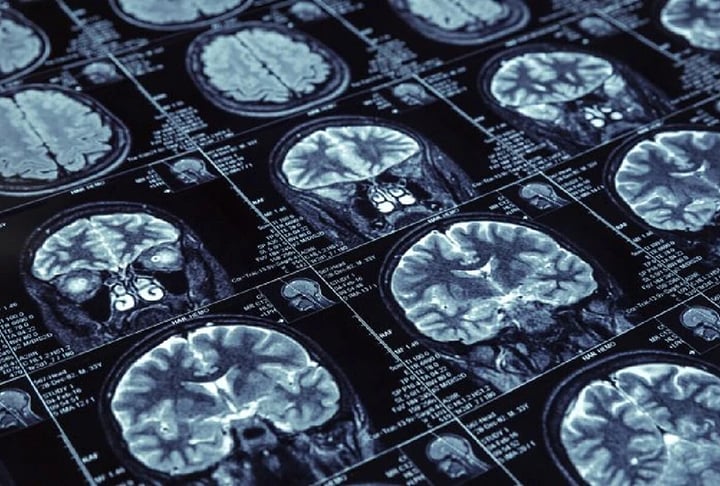

Primeira paciente vítima de Alzheimer entrou para a história